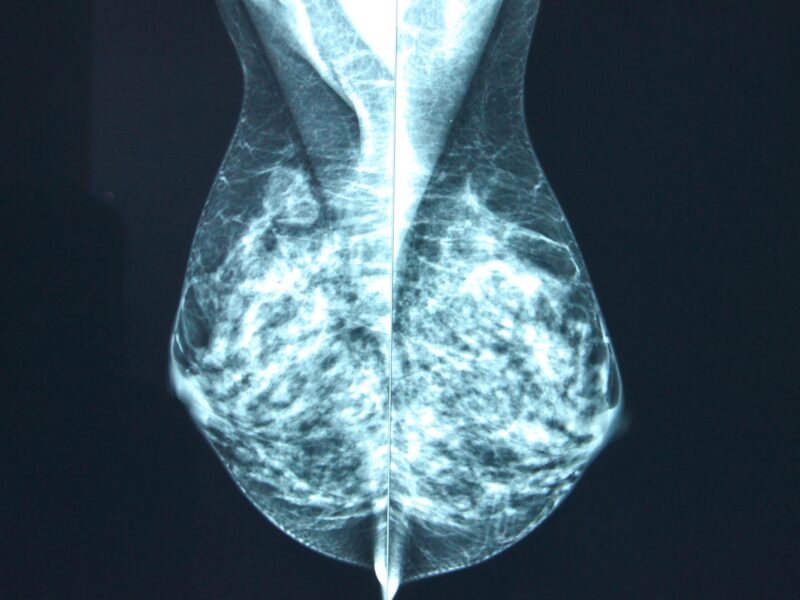

L’impact de ce protocole a été évalué et les résultats de l’IRM ont ensuite été analysés par deux radiologues séniors à l’aide de l’indice d’endométriose pelvienne profonde (dPEI) pour déterminer l’emplacement des lésions © Solenn Duplessy